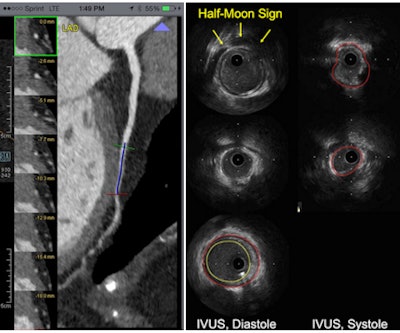

It is the widely varying presentations and implications of myocardial bridges that make imaging important. Some myocardial bridges barely touch the left ventricle and not the myocardium, while others are completely encased by the myocardium, as evidenced by a thickened layer of myocardium surrounding the coronary artery at CT, Becker said.

IVUS has its own ways of depicting a myocardial bridge, notably the echolucent half-moon sign, an area surrounding the coronary artery that is translucent and varying in thickness depending on the thickness of the myocardial bridge, he said.

But IVUS and CT were very well-correlated with regard to vessel encasement seen on CT and the thickness of the halo sign in MR, particularly if there was full encasement at CT. The halo-sign thickness on IVUS tended to be in the range of 0.8 mm.

"Similarly, we found good agreement between the measurements derived from CT and IVUS in terms of the distance from the circumflex to the bridge, as well as the length of the bridge itself, so these two modalities can be compared quite well for the assessment of these measurements," he said.